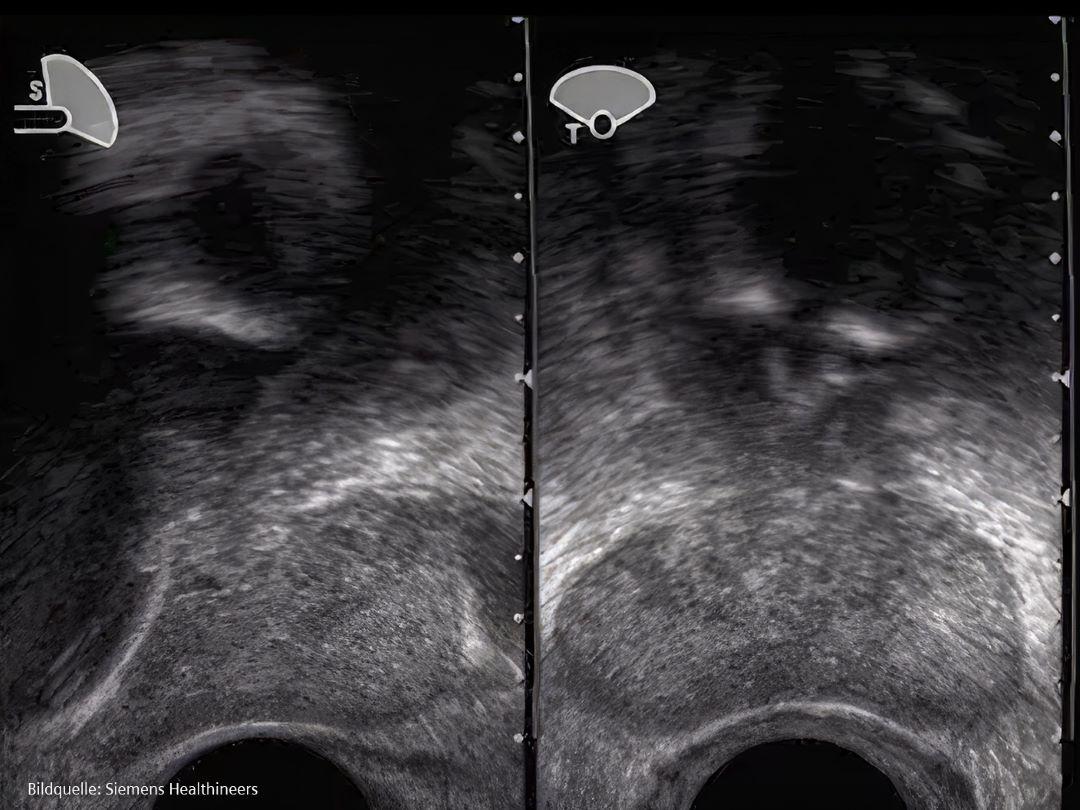

• Transrektale Ultraschall (TRUS)-gesteuerte systematische Biopsie

Bei einer transrektalen Ultraschall (TRUS)-gesteuerten Biopsie wird eine Nadel mittels Ultraschall geführt, um Gewebeproben von 12 Stellen in der Prostata zu entnehmen, hauptsächlich aus dem hinteren Bereich.

Bei der Brachytherapie werden dem Patienten radioaktive Strahlenquellen eingesetzt, um Krebszellen abzutöten. Bei Prostatakrebs im Frühstadium werden die radioaktiven sogenannten Seeds mit Hilfe von Nadeln in der Prostata platziert. Die Platzierung der radioaktiven Seeds in der Prostata wird durch Bilder aus dem transrektalen Ultraschall oder der Computertomographie gesteuert.